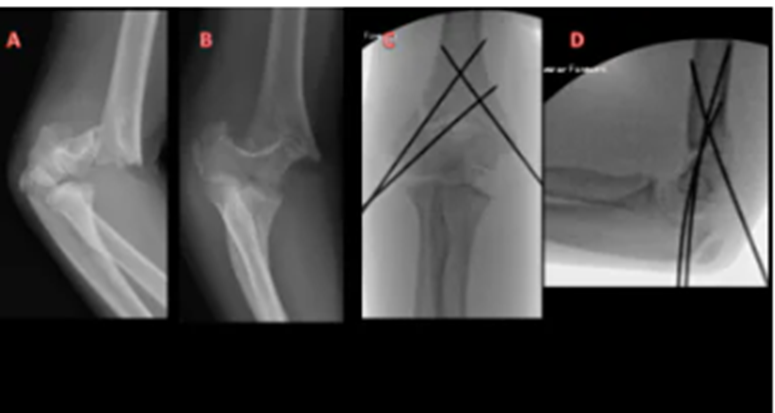

Hình 3.1.2:  A,B :Phim chụp khớp khuỷu ở bệnh nhân nam 5 tuổi gãy trên lồi cầu xương cánh tay Gartland IIb . C,D: Phim sau chụp của cùng bệnh nhân, sử dụng hai đinh Kirschner phía ngoài